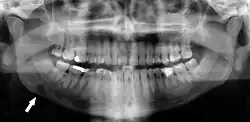

Dental infection and atherosclerosis

Atherosclerosis is attributed to risk factors that include cigarette smoking, hyperlipidemia, obesity, diabetes mellitus, and hypertension (high blood pressure). These factors, however, do not fully account for the risk of disease. Atherosclerosis has been conceptualized as a chronic inflammatory response to endothelial cell injury[24] and dysfunction possibly arising from chronic dental infection. In 2010, using the previously validated Mattila panoramic radiographic index to quantify the totality of dental infection (i.e., periapical and furcal lesions, pericoronitis sites, carious tooth roots, teeth with pulpal caries, and vertical bony defects), Friedlander's group determined that individuals with carotid artery atheromas on their panoramic radiographs had significantly greater amounts of dental infection/inflammation than atherogenic risk-matched controls devoid of radiographic atheromas.[25][26] While the Mattila index had been previously used to relate the extent of dental infection to coronary artery disease, this research is the first to link the full range of dental disease that it measures to panoramic radiographs evidencing calcified carotid artery atherosclerosis.